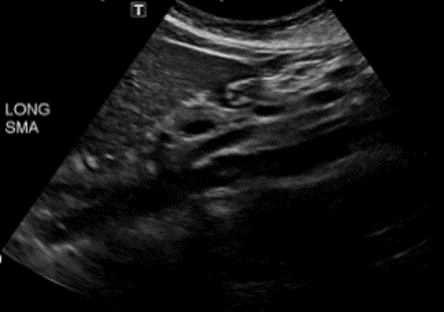

<p>In this sagittal plane, what is this structure?</p>

In this sagittal plane, what is this structure?

Aorta

In the longitudinal view, what is visualized of the SMA?

Run parallel to Aorta, and may course slightly to the right

In the transverse view, what is visualized of the SMA?

Dense echogenic ring of connective tissue / fat